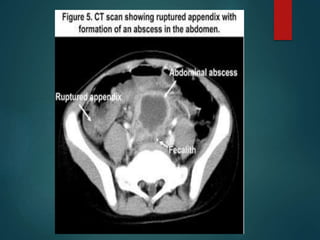

• Localized / Diffuse.

• Types ... Bacterial

Granulomatous,

Chemical

• CT .....

Peritonitis..

 Thickening &enhance

...peritoneum/omentum /mesentery

 Increased density of the mesenteric fat

Ascites

• #27 Peritonitis is an inflammation of the peritoneum that can result from numerous causes and can be either localized or diffuse. The major types of peritonitis include bacterial. primary, it usually results secondarily from perforation of an abdominal viscus. Common etiologies include appendicitis, diverticulitis, perforated ulcer, perforated carcinoma, acute cholecystitis, pancreatitis, salpingoopheritis, and abdominal surgery This CT appearance is nonspecific and can also be seen in patients with metastatic cancer or peritoneal mesothelioma